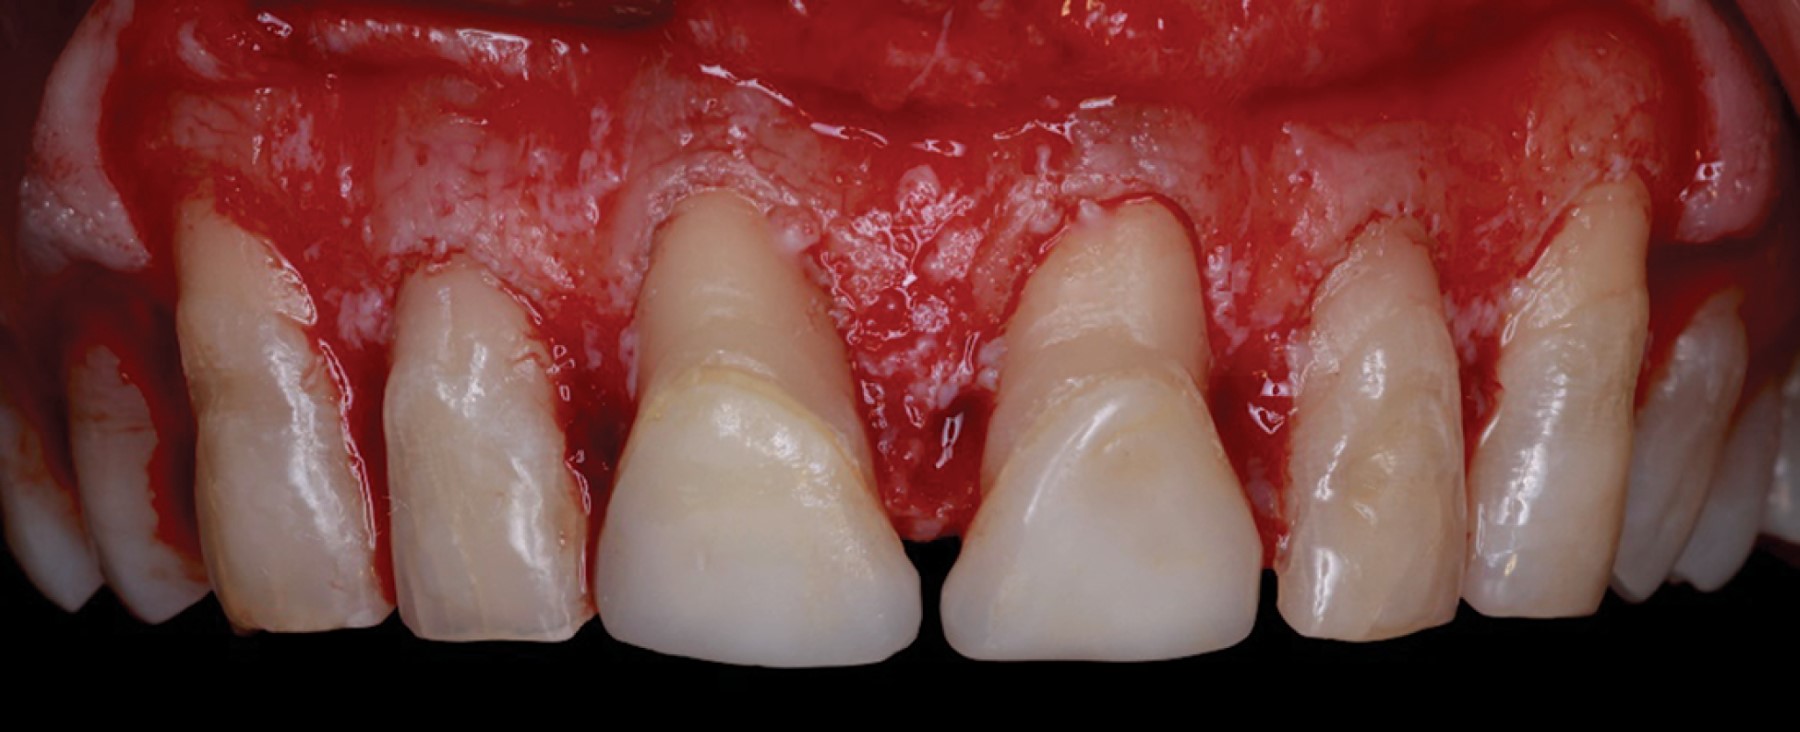

Introduction: crown lengthening for aesthetic purposes aims to reveal an adequate crown length and reduce gingival exposure. The procedure includes gingivectomy and alveolectomy to restore the prosthetically required supracrestal gingival tissue according to physiological dimensions. Through an intraoral scan of the maxilla, mandible, and maximum intercuspidal position, and using specialized software, the shape of the teeth and the gingival contour are digitally designed. This design generates an image of the desired aesthetic restoration for the prosthodontist and periodontist. The physical fabrication of the design is computer-assisted (CAD-CAM), creating a vacuum-formed acrylic resin surgical guide to determine the clinical crown length required in surgery. Objective: the presented interdisciplinary case describes an innovative technique using digital workflow through software that, from an oral scan, digitally designs a Mock-Up used as a guide for periodontal surgery. Case presentation: a 52-year-old ASA I patient attended the Periodontics Master's clinic at Universidad Autónoma de Coahuila (UAdeC) for periodontal surgery with aesthetic purposes. The surgery was performed by placing the Mock-Up in the anterosuperior region as a guide for gingivectomy. Then, a flap was raised before the alveolectomy, considering the length of the supracrestal gingival tissue. Finally, the soft tissues were sutured with a horizontal mattress suture technique. Results: seven days later, the sutures were removed, showing correct and uniform tissue healing. Conclusions: this digital approach offers a significant reduction in surgical time, in addition to satisfactory esthetics and precise gingival architecture.

Figure 1